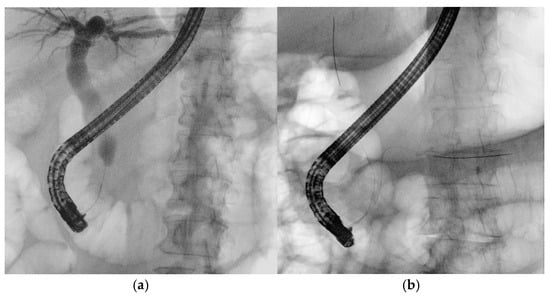

3.1. Biliary Duct Cannulation

Guidewires are essential in the early stages of ERCP. A pivotal 2004 study by Fausto Lella demonstrated the superiority of wire-guided cannulation (WGC) over contrast-assisted methods [21]. The WGC technique has widely become the first-line approach to biliary cannulation [22]. Both techniques require fluoroscopy, as guidewires, like contrast agents, have a radiopaque core visible on radiological images. In WGC cannulation, the guidewire is introduced through the papilla using a sphincterotome or cannulotome, and fluoroscopy enables real-time visualization for selective biliary or pancreatic duct cannulation (Figure 4a). Studies show that this technique increases the success rate, reduces papillary trauma, and minimizes contrast injection into the Wirsung duct, lowering post-ERCP pancreatitis rates [23]. A meta-analysis of RCTs confirmed that WGC cannulation significantly improves biliary cannulation rates (OR: 2.05, CI: 1.27–3.31) and decreases post-ERCP pancreatitis (OR = 0.23, CI: 0.13–0.41) [24]. In the case of trainees, who often take longer to perform ERCP, an RCT indicated that angled guidewires led to higher successful selective biliary cannulation rates compared to straight guidewires. The limitations of the study are the small sample size and the definition of difficult biliary cannulation set at 7 min, which could be equivocal [25]. The typical WGC involves loading a straight guidewire onto a sphincterotome, but for trainees with limited experience, the angle of an angled one can assist in achieving successful cannulation. A recent RCT involving 588 patients compared exclusive WGC with the hybrid technique, in which small amounts of contrast are injected into the distal bile and pancreatic ducts when the infundibulum of the papilla of Vater is cannulated to help orient the papillotome or guidewire axis toward the biliary tree. The results of this study showed faster biliary cannulation, a shorter total ERCP time, reduced need for precut, and less inadvertent intubation of the Wirsung duct, which was identified as a greater risk factor for PEP than inadvertent contrast injection into the pancreatic duct (OR 4.22 vs. 2.63). However, along with these potential beneficial factors, PEP occurred at similar rates in both groups. The limitations of the study include its single-center design, the lack of a standardized threshold for precutting, and the absence of prophylactic measures in both groups [26]. Selective biliary cannulation using conventional techniques fails in up to 18% of native papilla cases [22]. In difficult cases, the “double guidewire technique” (DGW-T) is often employed, where one wire is placed in the Wirsung duct to block the pancreatic orifice, aiding the second wire in cannulating the bile duct (Figure 4b). This technique also helps in identifying papillary anatomy and orienting biliary access [27].

Figure 4. (a) Wire-guided cannulation in ERCP; (b) double-guidewire technique: the first guidewire is positioned in the main pancreatic duct, followed by placement of the second guidewire into the biliary duct.